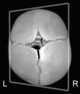

Unilateral lambdoid craniosynostosis

Craniosynostosis is a condition in which one or more of the fibrous sutures in an infant (very young) skull prematurely fuses by turning into bone (ossification), thereby changing the growth pattern of the skull. Because the skull cannot expand perpendicular to the fused suture, it compensates by growing more in the direction parallel to the closed sutures. [Source: Wikipedia ]